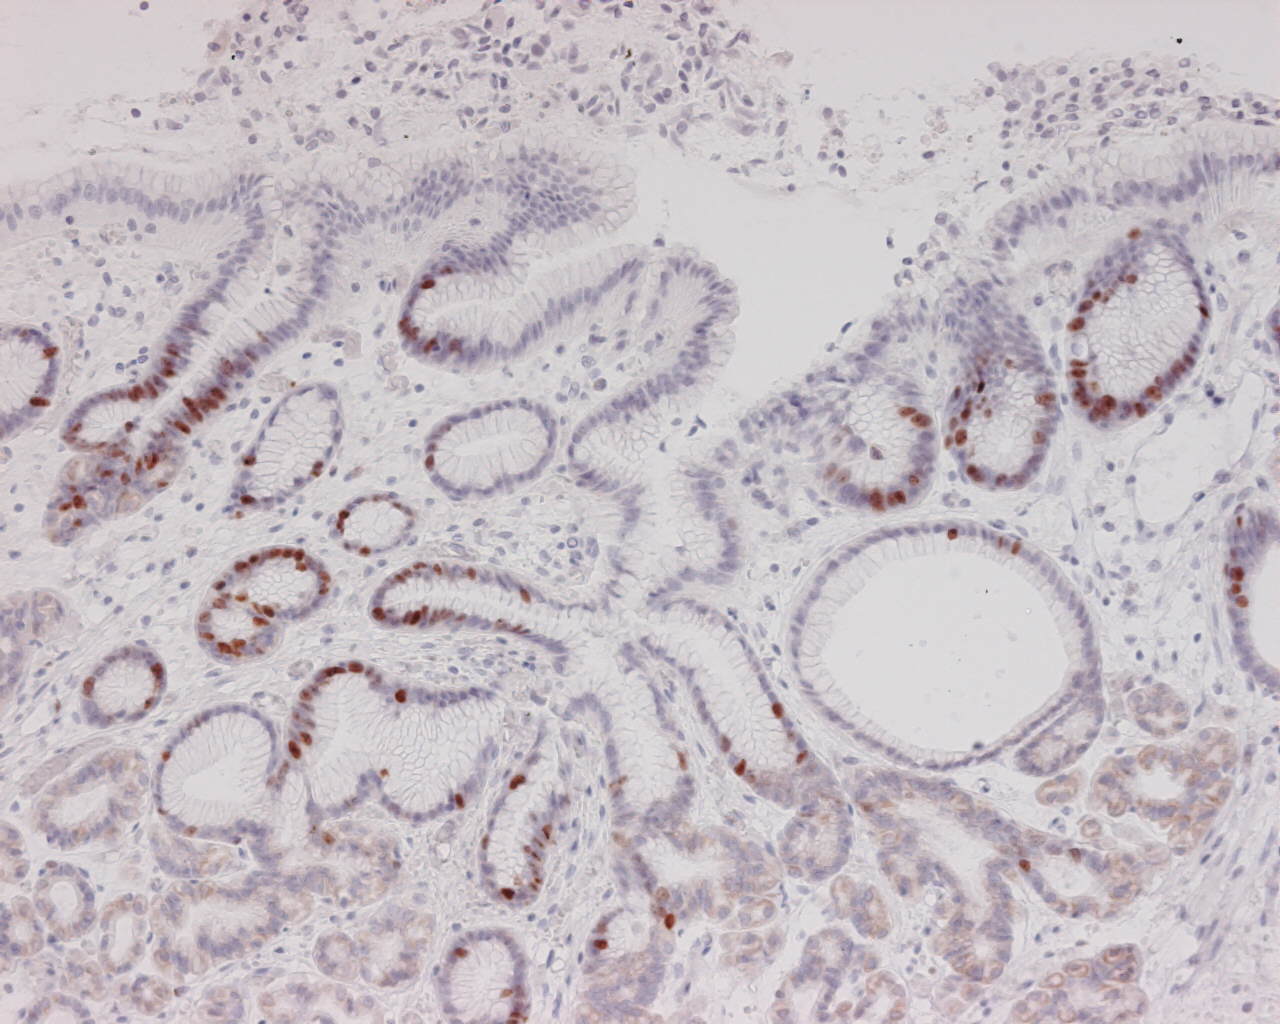

胃癌相关基因βcatenin、apc、siah1、cyclin d1的研究. 胃癌相关基因βCatenin、apc、siah1、cyclin d1的研究,尤立光;邹小明;黑龙江医药2007年第04期杂志在线阅读、文章下载。. 胃癌组织dcc, apc_mcc 基因杂合性缺失研究_百度文库. 胃癌组织Dcc, apc_mcc 基因杂合性缺失研究_医药卫生_专业资料。胃癌组织dcc, apc_mcc. Airiti library華藝線上圖書館. 山東臨朐胃癌高發人群和北京人群Lewis血型抗原 apc基因 ; i1307k突變 ; 蛋白質 ; 胃癌 ; apc gene ; i1307k mutation ; protein. Apc(肿瘤抑制基因apc)_百度百科. Alternative personal home page cache(apc personal home page 据报道apc的1a启动子区高甲基化也发生在胃肠癌症中,比如食管癌,胃癌. 早期胃癌に対するアルゴンプラズマ凝固療法(apc)の組織学的効果 論. 早期胃癌に対するアルゴンプラズマ凝固療法(Apc) (pgi) の胃癌組織中の局在と、その腫瘍マーカーとしての意義. 胃癌组织dcc, apc_mcc 基因杂合性缺失研究.Pdf 豆丁网. 胃癌组织Dcc, apc_mcc 基因杂合性缺失研究.Pdf. Memedhuya16.

多重pcr和dna测序技术检测胃癌apc基因15外显子突变. 多重Pcr和dna测序技术检测胃癌apc基因15外显子突变,目的 探讨apc基因突变在胃癌发生中的作用及微卫星dna不稳的关系。方法. 胃癌中apc基因i1307k突变及蛋白质表达 万方数据中小学数字图书馆. 摘要. 为探讨肿瘤抑制基因Apc结构及表达异常与胃癌发生、发展的关系,采用arms pcr检测胃癌中apc基因i1307k突变存在与否,免疫. 胃癌相关基因βcatenin、apc、siah1、cyclin d1的研究《黑龙江医药. 胃癌相关基因βCatenin、apc、siah1、cyclin d1的研究,尤立光;邹小明;黑龙江医药2007年第04期杂志在线阅读、文章下载。. 【内視鏡治療】千葉大学大学院医学研究院先端応用外科. レーザー治療、アルゴンプラズマ凝固( Apc )療法 さまざまな合併疾患によって消化器癌(食道癌、胃癌. Apc(肿瘤抑制基因apc)_百度百科. Opportunity personal home page cache(apc personal home page 据报道apc的1a启动子区高甲基化也发生在胃肠癌症中,比如食管癌,胃癌. 多重pcr和dna测序技术检测胃癌apc基因15外显子突变. 多重Pcr和dna测序技术检测胃癌apc基因15外显子突变,目的 探讨apc基因突变在胃癌发生中的作用及微卫星dna不稳的关系。方法. 胃癌 疾病 丁香医生 dxy. 胃癌的预后与胃癌的病理 与胃癌发生相关的癌基因包括:Ras基因、bcl2;抑癌基因包括:野生型p53、apc、dcc、mcc等;生长. Apc基因在胃癌、癌前病变及胃腺瘤中表达意义的研究_文库下载. 目的 探讨Apc基因在胃癌及胃腺瘤发生、发展中的重要作用以及在胃癌早期诊断中的意义。.